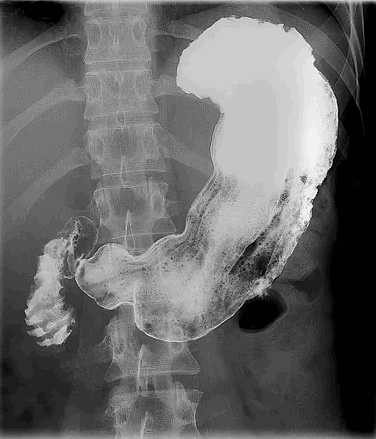

Рентгеноскопия желудка – это диагностическое исследование, представляющее собой неинвазивную методику, которая даёт возможность исследовать форму, размеры, положение пищевода, желудка и 12-перстной кишки, а также выявить их анатомические особенности и патологические изменения.

Желудок – это орган брюшной полости с полой структурой. Для выполнения объективного рентгенологического исследования используется дополнительное контрастирование водным раствором сульфата бария в количестве 250-300 мл, который безвреден для организма пациента, не всасывается в желудочно-кишечном тракте и выводится в неизмененном виде.

Иногда при необходимости исследования внутренней поверхности желудка и антрального отдела применяется двойное контрастирование.

При проведении исследования, которое длится 30-40 минут, врач обязательно оценивает прохождение контрастной массы по пищеводу, желудку и 12-перстной кишке, отмечает изменения и производит рентгеновские снимки. Они обрабатываются в конце исследования и дают возможность рентгенологу правильно оценить состояние исследуемых органов и поставить диагноз.

Рентгеноскопия пищевода + рентгенография (как отдельное исследование):

Чтобы правильно поставить диагноз, учитывая жалобы пациента, рентгенолог проводит самостоятельное исследование пищевода. Для этого пациенту дается несколько глотков бариевой взвеси и проводится серия полипозиционных (в разных положениях: боком, косо справа и слева, лежа и стоя) снимков под прицелом RG-скопии. Оценивается форма, положение пищевода в грудной полости, скорость прохождения бариевой взвеси, расположение складок слизистой, дополнительные сужения или выпячивания в стенке пищевода (дивертикулы). При исследовании пищевода врач может обнаружить грыжу пищеводного отверстия диафрагмы, оценить ее размеры и положение, что подскажет кардиологам и гастроэнтерологам план дальнейшего лечения больного.